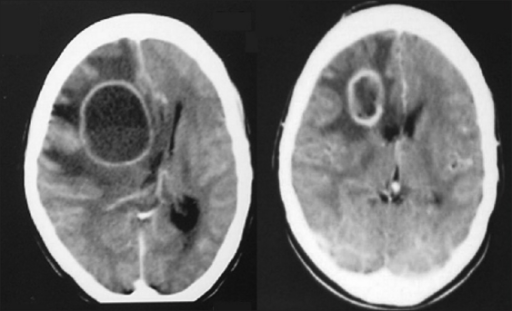

Normal brain ct scan & hydocephalus

Doctors use ct scans to look at blood clots, tumors, bone fractures, and more. Why is ct blood white? The lecture shows the basic ct anatomy of the brain. Ct principle ring of xray detectors 3.